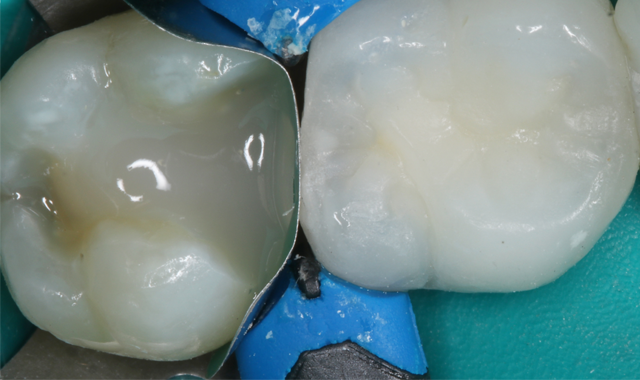

Fig. 5

Fig. 6

A Compsi-Tight™ 3D Ring with a SlickBand™ and WedgeWand® (Garrison) were used to replace the missing tooth surface and form the adaptive layer of composite restoration. It is very important in this step to have a tight interface between the band and tooth to allow for ultimate adaptation of the direct restoration to the margins (Fig. 5).

Fig. 7

The next step was the selective etching technique, utilizing 35% phosphoric acid (Ultra-Etch®, Ultradent) on enamel only. The etch was applied on the enamel for 15 seconds and rinsed thoroughly (Fig. 6).

A universal adhesive was scrubbed on the selectively etched tooth per manufacturer’s instructions using Adhese® Universal in the VivaPen® delivery (Ivoclar Vivadent) (Fig. 7).